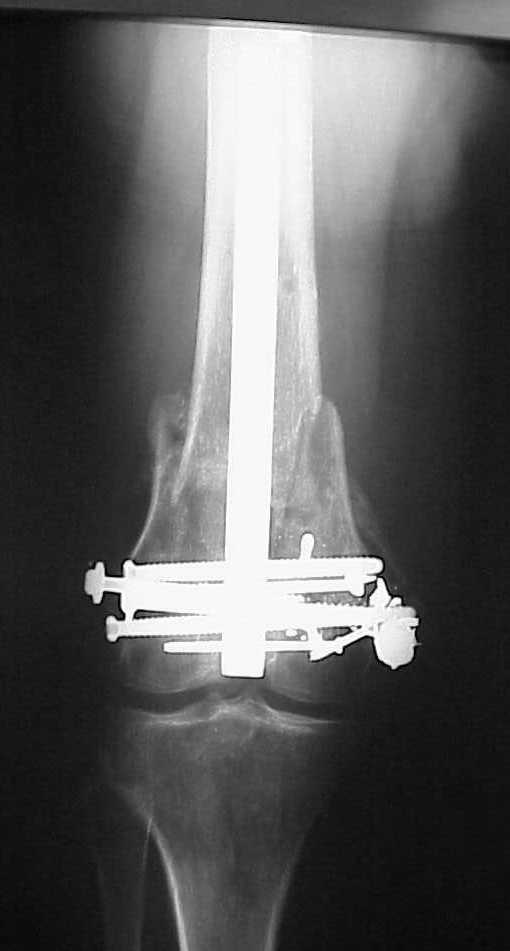

See attached case that was done several years ago before LISS. He had comminuted trochlea and anterior blocking screws were used to prevent anterior IMN cut-out.